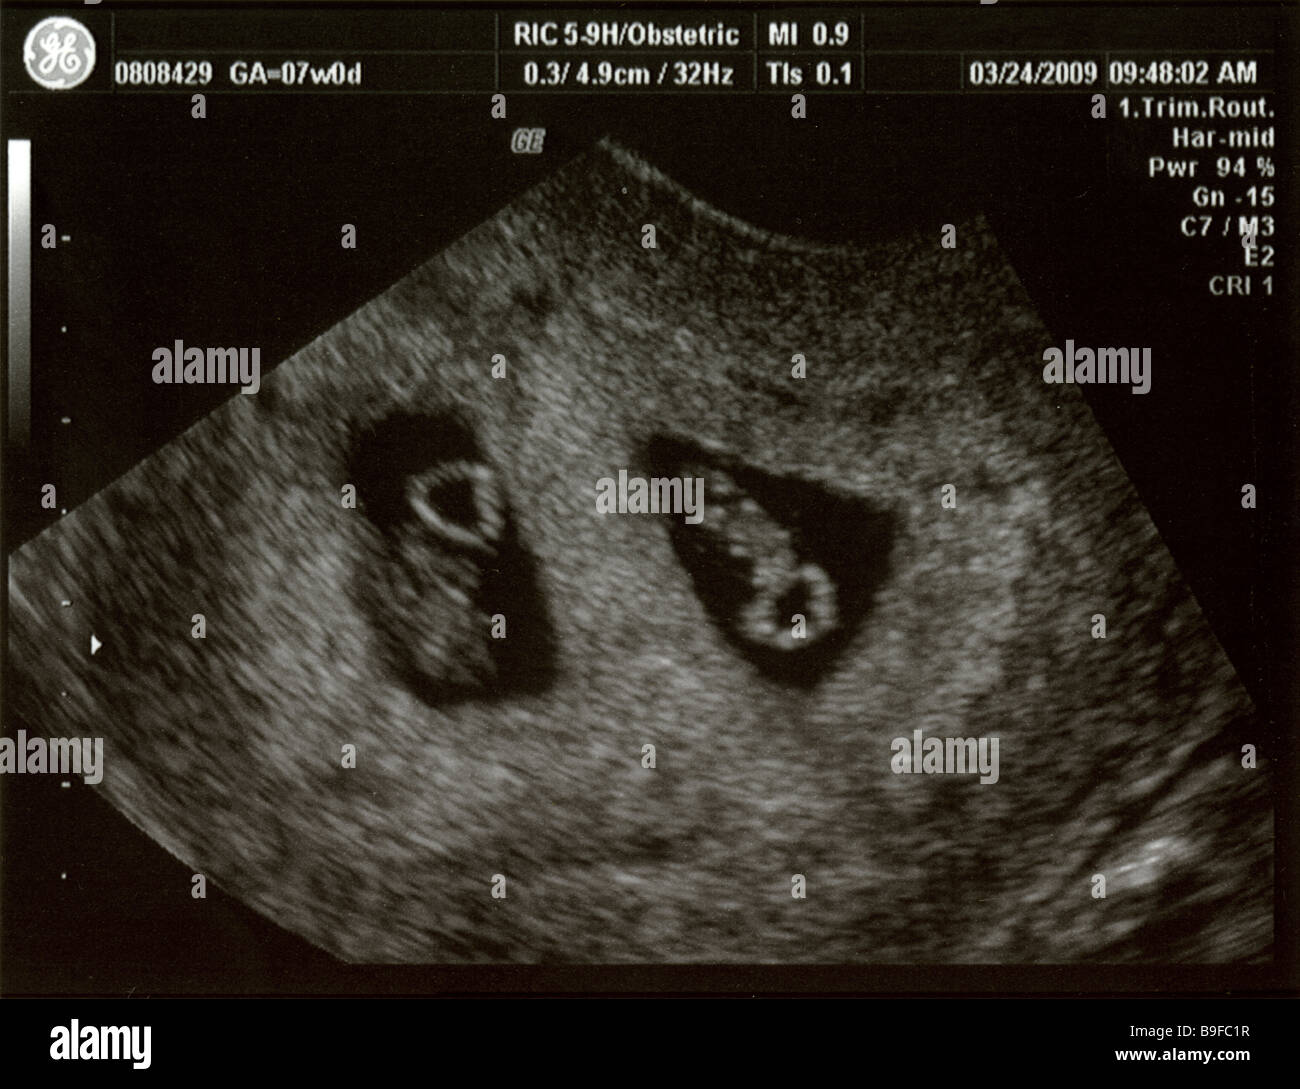

5 Weeks Pregnant with Twins – Twiniversity

Ultrasound showing foetal development of fraternal twins at 7 weeks …